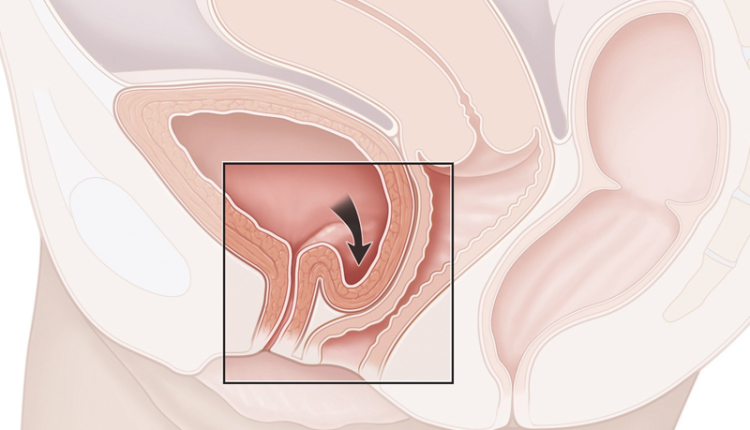

Sa bàng quang độ 3

Tiến sĩ bác sĩ Lê Phúc Liên, Trưởng Đơn vị Niệu nữ, Trung tâm Tiết niệu – Thận học – Nam khoa, cho biết người bệnh đến khám vì tình trạng tiểu không kiểm soát khi gắng sức (ho, hắt hơi, cười lớn, mang vác nặng…). Mức độ són tiểu ở mức trung bình, phải thay quần lót 3-4 lần mỗi ngày. Tuy nhiên, khi thăm khám, bác sĩ phát hiện thêm người bệnh bị sa bàng quang độ 3. Đây là nguyên nhân khiến tình trạng són tiểu nặng hơn.

Sa bàng quang là tình trạng thay vì ở vị trí đúng trong vùng chậu, cơ quan này tụt xuống âm đạo và sa ra ngoài. Nếu không điều trị sớm, bàng quang có thể sa ra ngoài hoàn toàn (độ 4). Lúc này, khối sa có thể lở loét, nhiễm trùng do cọ xát với quần áo, cơ thể. Ngoài biến chứng són tiểu, người bệnh có nguy cơ bí tiểu, thận ứ nước, suy thận. May mắn, người bệnh khi nhập viện chưa có các biến chứng này.